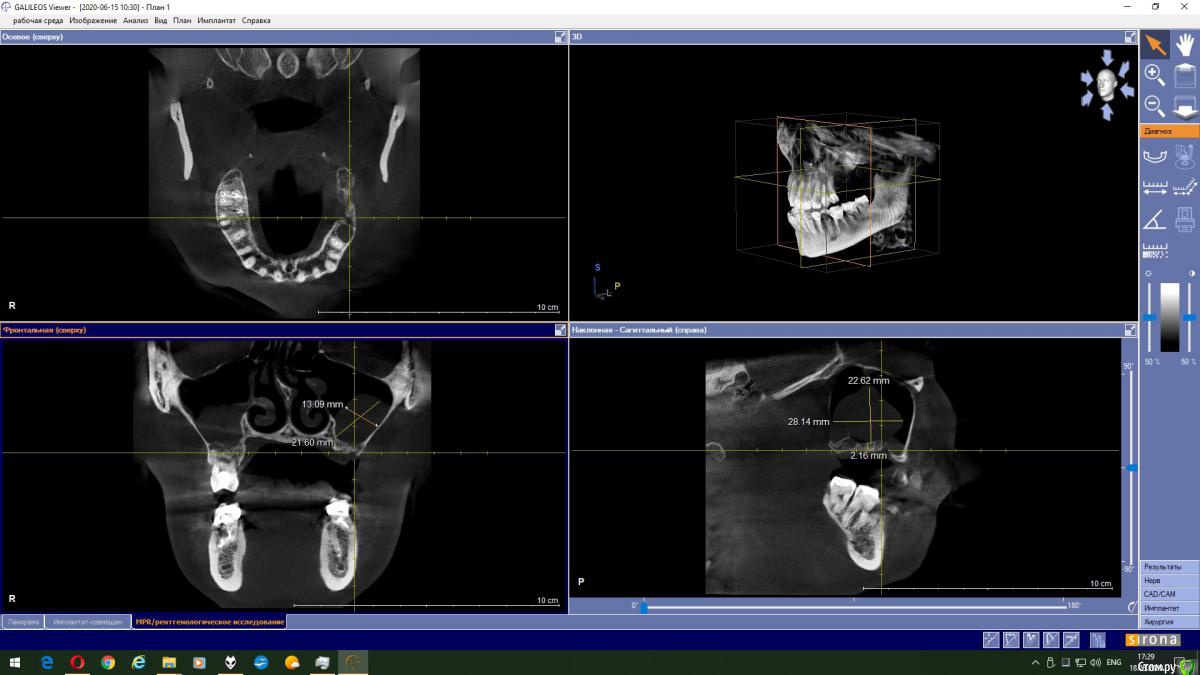

Magnoliya Опубликовано 18 июня, 2020 Поделиться Опубликовано 18 июня, 2020 Здравствуйте, прошу Вашей помощи и консультации. Все доктора, у которых я уже побывала говорят противоположные вещи, сложно принять решение. Очень надеюсь, что вы сможете посмотреть КТ, и выскажете своё мнение. http://fayloobmennik.cloud/7398744 Предыстория удалила 6 и 7 на левой верхней челюсти в надежде, что через 4 месяца сделаю открытый синус-лифтинг с подсадкой костной ткани и затем установлю импланты,но когда принесла КТ врачу перед операцией, он сказал, что синус лифтинг противопоказан, так как в гайморовой пазухе киста, и костной ткани мало, от слова ОЧЕНЬ МАЛО. В его видении решении моей проблемы был скуловой имплант Zigoma. при котором сразу после операции я выйду с зубами, естественно с другой суммой на операцию, на которую я не расчитывала. Тут я решила пойти на консультацию к другим специалистам, чтоб принять решение. На сегодняшний день есть 3 варианта, которые озвучили мне доктора: 1. Операция со скуловым имплантом с одномоментной установкой коронок2. Обратиться к ЛОРу и удалить кисту, затем синус лифтинг и т.д.3. Один врач сказал мне, что киста не мешает и можно делать синус лифтинг не удаляя кисту??? Действительно ли так? Можно ли избежать операции по удалению кисты? Заранее спасибо всем тем, кто хоть как то поможет советом Ссылка на комментарий

колесников Опубликовано 18 июня, 2020 Поделиться Опубликовано 18 июня, 2020 Глупости какие! Для чего зигомы? Доктора видимо смутил рельеф дна пазухи,там много перегородок,выступов,что затрудняет отслаивание мембраны. Можно провести имплантацию одновременно с синуслмфтингом,а кисту и вовсе не трогать. 1 Ссылка на комментарий

Bier Опубликовано 18 июня, 2020 Поделиться Опубликовано 18 июня, 2020 Данную кисту убирать не нужно. Нет показаний для зигомы. Делайте синуслифтинг и имплантат. Ссылка на комментарий

колесников Опубликовано 19 июня, 2020 Поделиться Опубликовано 19 июня, 2020 Выходить можно сделать синус лифтинг не трогая кисту. В дальнейшем ничем это не грозит? Я имею ввиду киста не вытечет на импланты? И может ли киста со временем рассосаться сама? это не инфекционного происхождения киста,слизистая железка закупорилась,может надуваться,может лопнуть самостоятельно,у вас она на боковой стенке пазухи,синуслмфтингу не помеха Ссылка на комментарий